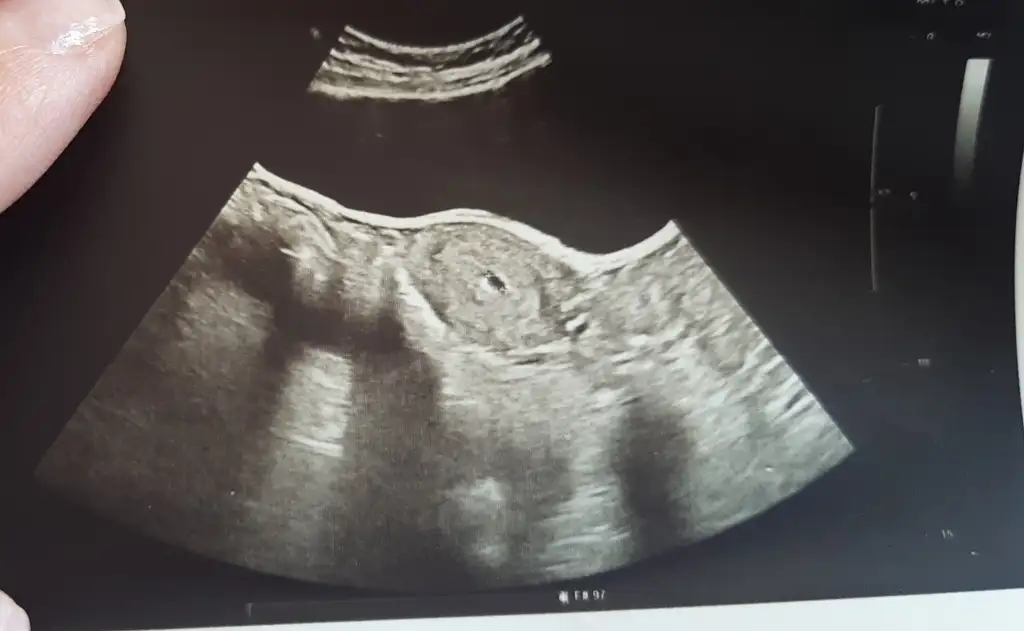

Benim de dün kesem gözüktü 6.77 mm beş haftalık dedi doktor daha önce boş gebelik geçirmiştim sizin kesezin içi dolu mu gözüküyor mu yaniEvet 5 haftalik boyutu da 5 mm

Evet gorunuyor bugun gitmistim 7+3 um 1.17 cm olculdu ve kalp atislarini duydukBenim de dün kesem gözüktü 6.77 mm beş haftalık dedi doktor daha önce boş gebelik geçirmiştim sizin kesezin içi dolu mu gözüküyor mu yani

Bugün mü göründü peki yoksa beşinci haftada mıEvet gorunuyor bugun gitmistim 7+3 um 1.17 cm olculdu ve kalp atislarini duyduk

5.hafta da ultrason goruntusunde cok net degil zaten ama gorunmese mm i hesaplanmazdi sanirim. Benim 5mm di ilk keseyi gordugumdeBugün mü göründü peki yoksa beşinci haftada mı

Bu 5 haftalik ultrason goruntumKese içi böyle boş mu gözüküyordu sizin

Bende benim ki ufak gibi geliyor dünden beri içim içimi yiyor yine gelişmez mi diye sizBu 5 haftalik ultrason goruntum